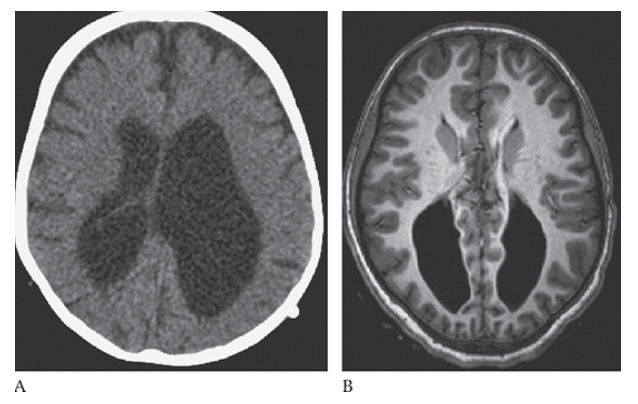

What is A

Agenesis of the Corpus Callosum. Axial CT and axial T1W MR

What is B

Agenesis of the Corpus Callosum. Axial CT show enlarged and parallel lateral ventricles with a “race car” configuration and no corpus callosum.